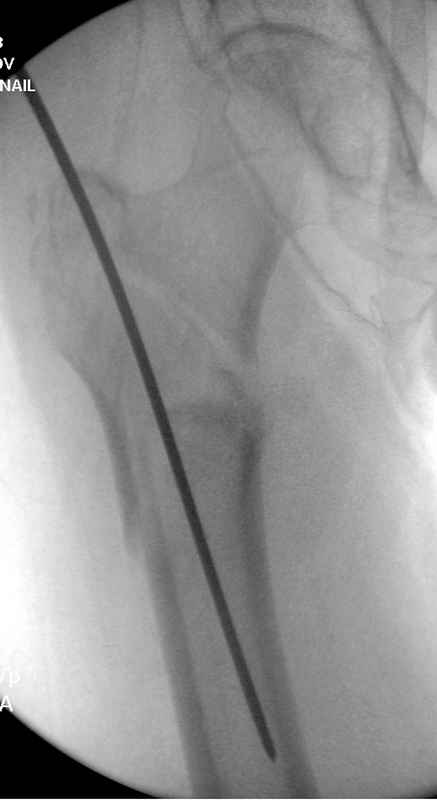

Здесь пара случаев фиксации похожих переломов:

первый высокоэнергетическая травма 36 лет

судя по картинкам с ЭОПа явно использовались приемы непрямой репозиции под его контролем, а так же интраоперационный ЭОП-контроль положения винтов, без такого контроля операция может ухудшить ситуацию (опять же учтите сроки) т.к. результат буде зависеть в большей степени от искусства хирурга, а не от технологии